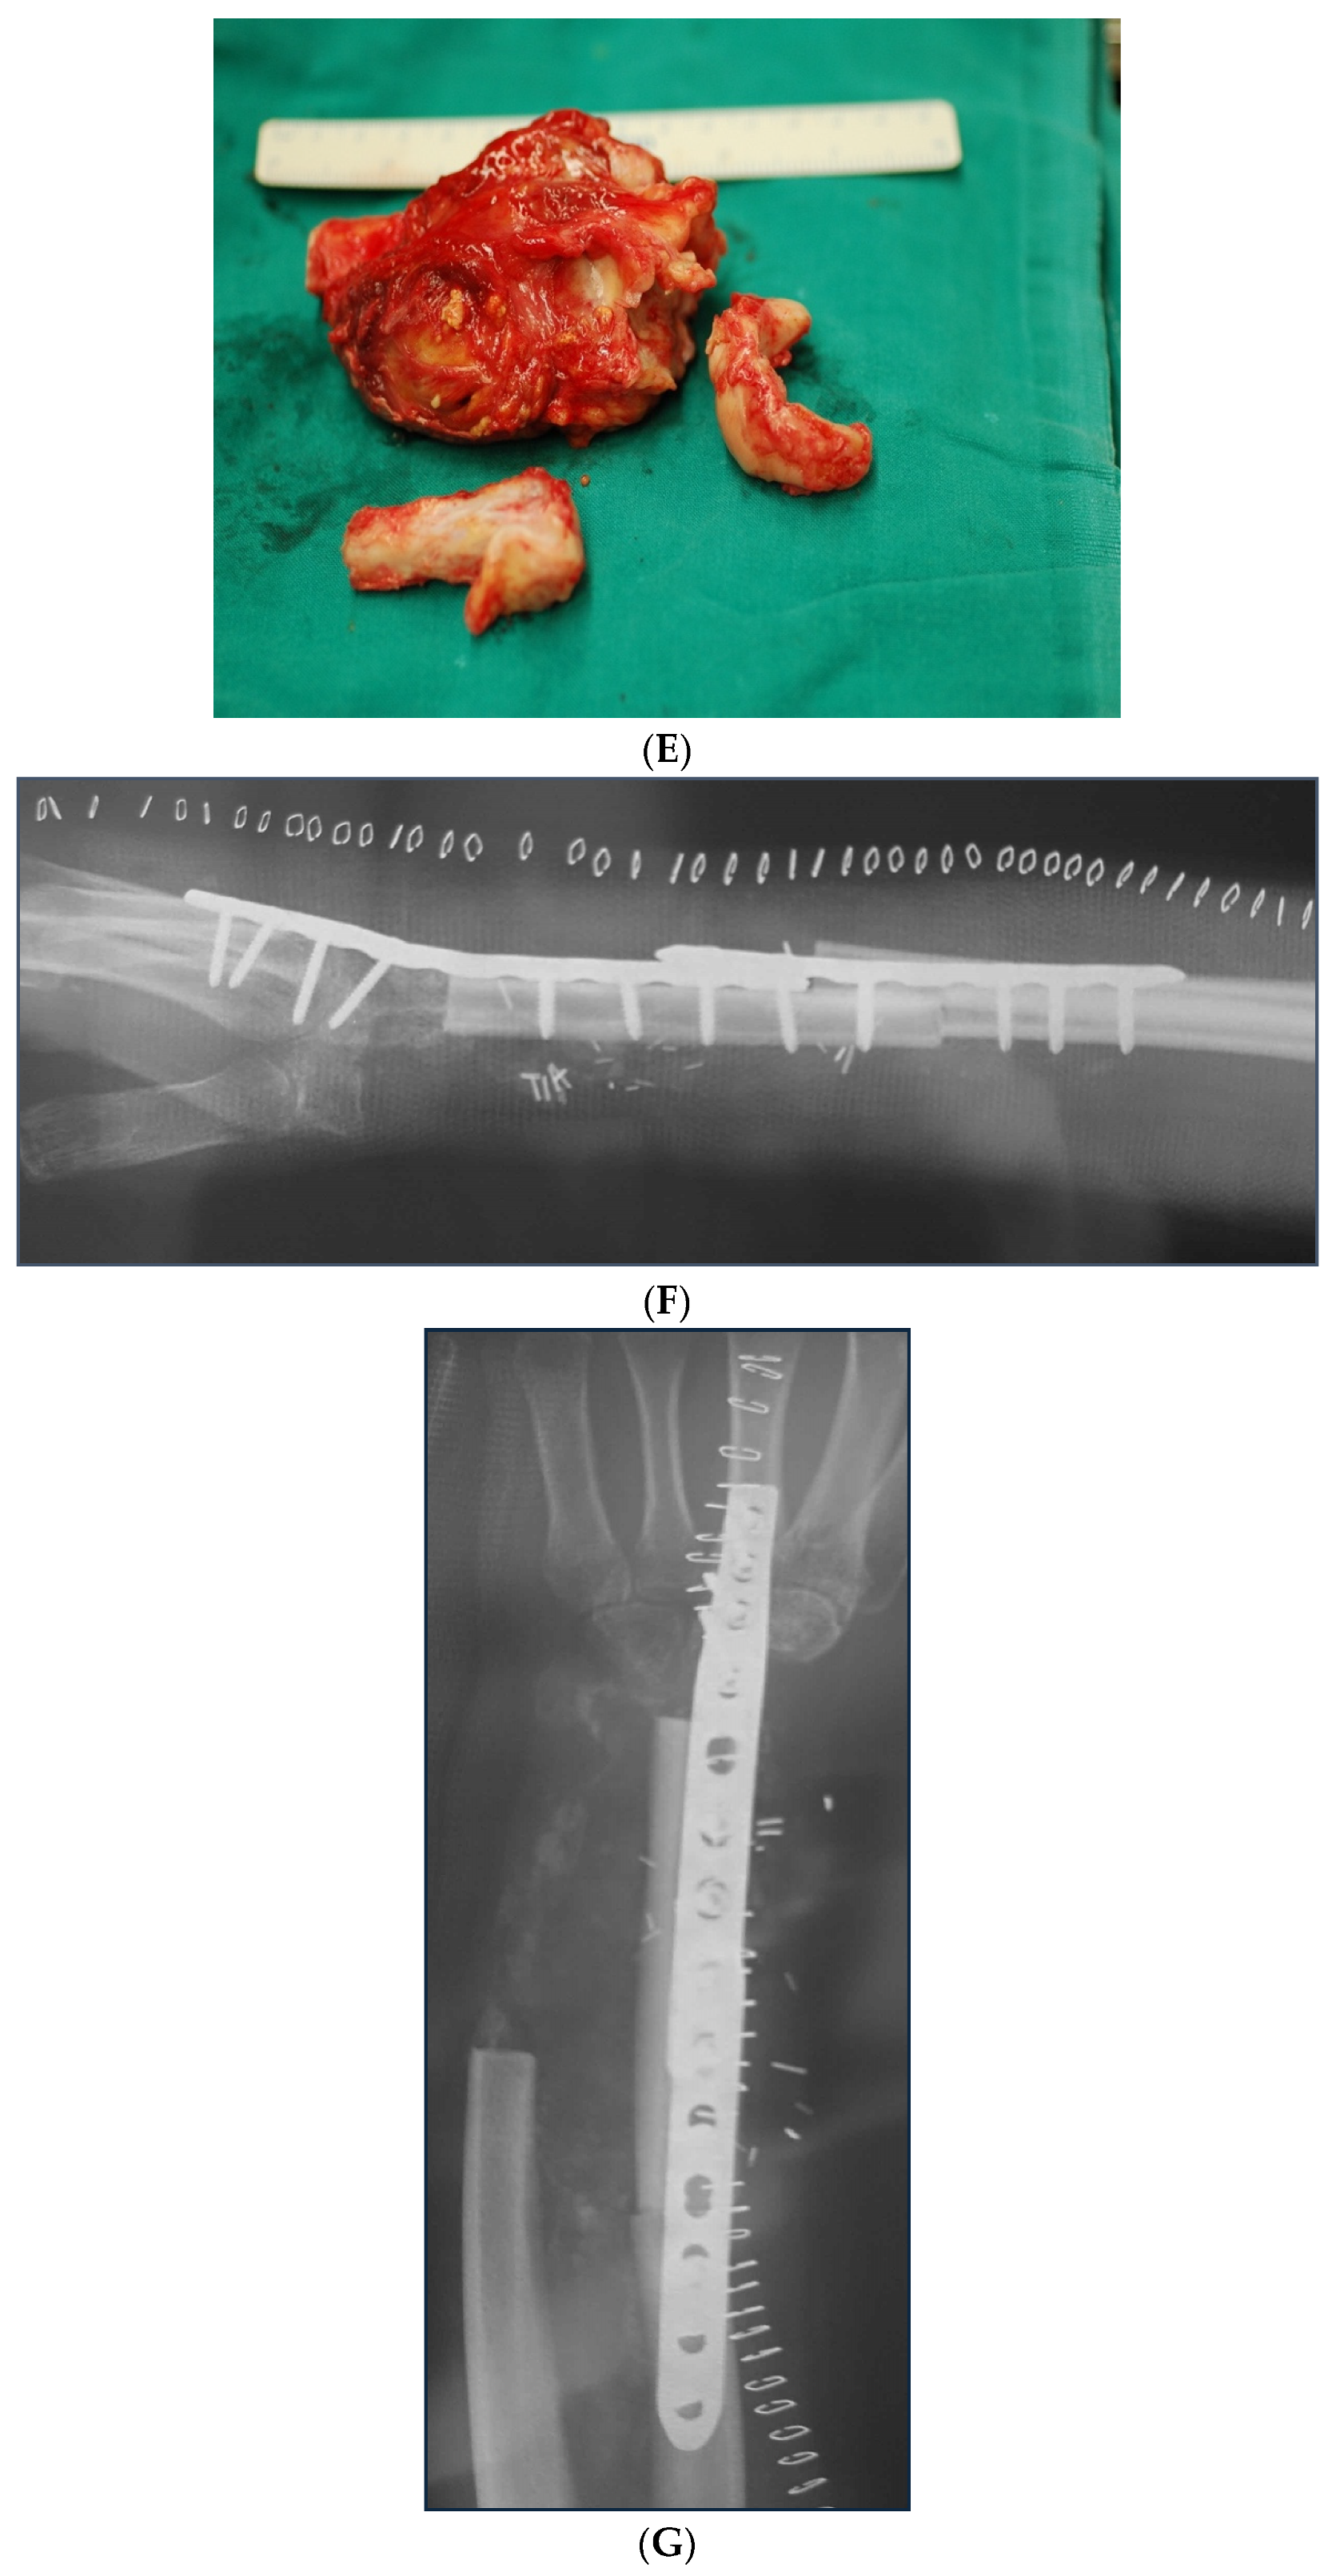

In cases of bone fracture non-union, the surgeon excised scar tissue along with the sequestrum until reaching bleeding bone, following the removal of previously inserted metalwork. For tumor excision cases, the surgeon resected the bone tumor with clear margins or the entire compartment in cases of tumor-induced bone cortex breakage (Figure 1). At this stage, the length of the bone defect was measured to determine the appropriate length of the fibular graft to be harvested (Figure 2). The fibular graft fixation was accomplished using dynamic compression plates (DCPs) or anatomical plates, with a minimum of six cortices engaged on each side using either simple or locking screws (Figure 3). Once the osteosynthesis is completed, it is time to proceed with the vessel anastomosis. First, the peroneal vein is anastomosed to the radial or ulnar vein using 8-0 nylon monofilament sutures. Following this, the surgeon performs the arterial anastomosis using the same type of suture as previously. Simple interrupted stitches are preferred over a continuous suture technique and the anastomosis could be either end to end or end to side using a microscope.

Figure 3. Large ulnar skeletal defect treated with FVFG, fixated using two LC-DCP plates.